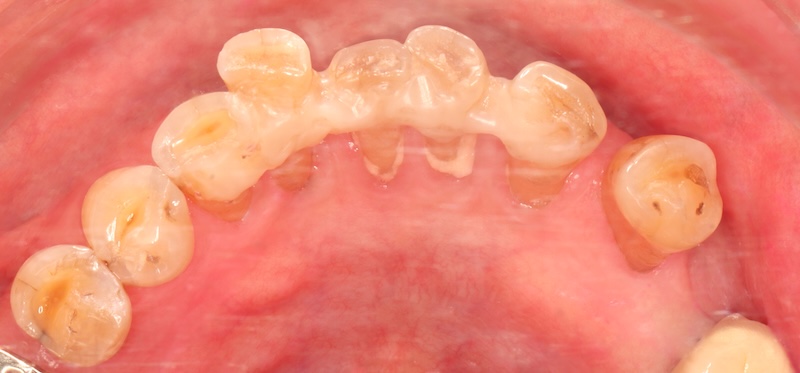

全鋯冠牙橋搭配全瓷貼片,解決前牙牙縫大

牙周治療過後的美容重建才是高難度的任務。幸好我們現在有數位化的輔助,能夠在還沒修牙齒、做假牙之前,就先讓患者初步試戴(mock up),體驗看看未來完成時的外貌。此時患者也能回饋自己的想法讓醫師和牙技師暸解,輔助我們在合理的範圍內修改到患者能接受的樣子。

討論定案後,我會依照共同決定的結果來修型,口內掃描後再由數位牙技師進行數位化電腦設計與製作。上顎牙橋是使用全鋯冠,其他牙齒則都使用全瓷貼片,將整體空間做好協調分配,完成之後順利地把所有牙縫幾乎都成功關閉。

上顎問題獲得解決之後,Ms.D 等不及要治療下面的牙齒。同樣的流程,我們也順利把下顎的全瓷貼片完成。

試戴流程利用複合樹脂置放在牙齒上,和患者溝通外型。如果有出現比較黃的牙齒顏色,代表牙齒本身位置比較突,這種情況牙齒會需要修得比較多一些,未來才有辦法同時改變牙齒的顏色和視覺上的排列位置: